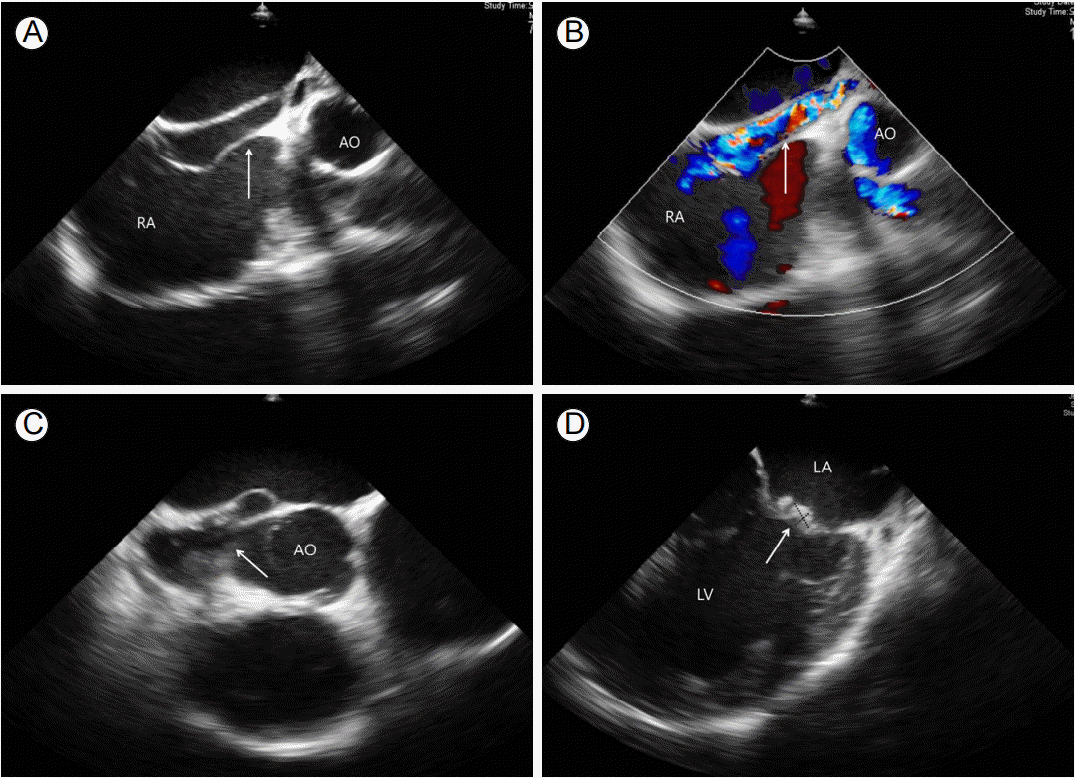

Figure 3.

Surgical findings revealed (A) a 2 mm sized vegetation in the aortic valve. (B) Insertion of a foley catheter in the right atrium hole. (C) Left sinus Valsalva out by foley.